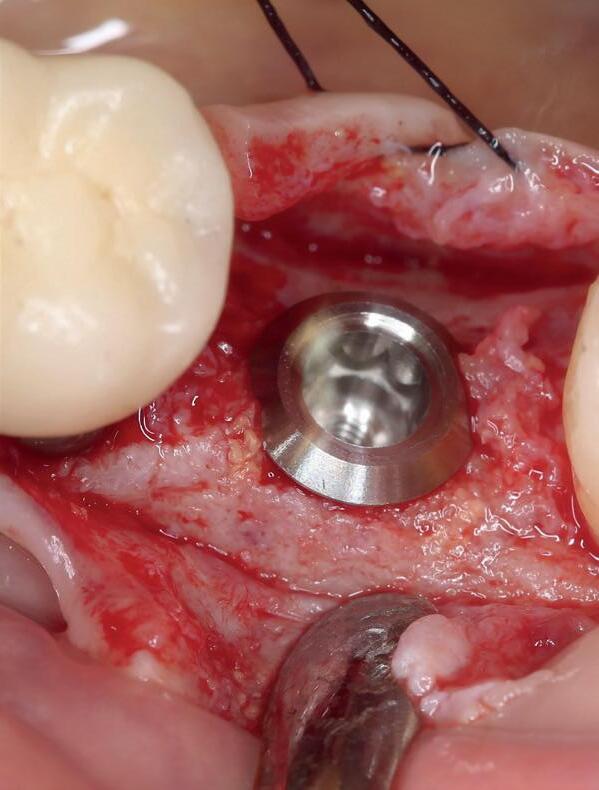

Zes maanden na extractie wordt het implantaat 37 geplaatst. Er is sprake van een goede genezing en de processushoogte en -breedte zijn behouden en opgebouwd. Ook is er zichtbaar gekeratiniseerd weefsel

gewonnen. De wond kan na het plaatsen van een healing abutment primair gesloten worden (Afbeelding 3a-3d).